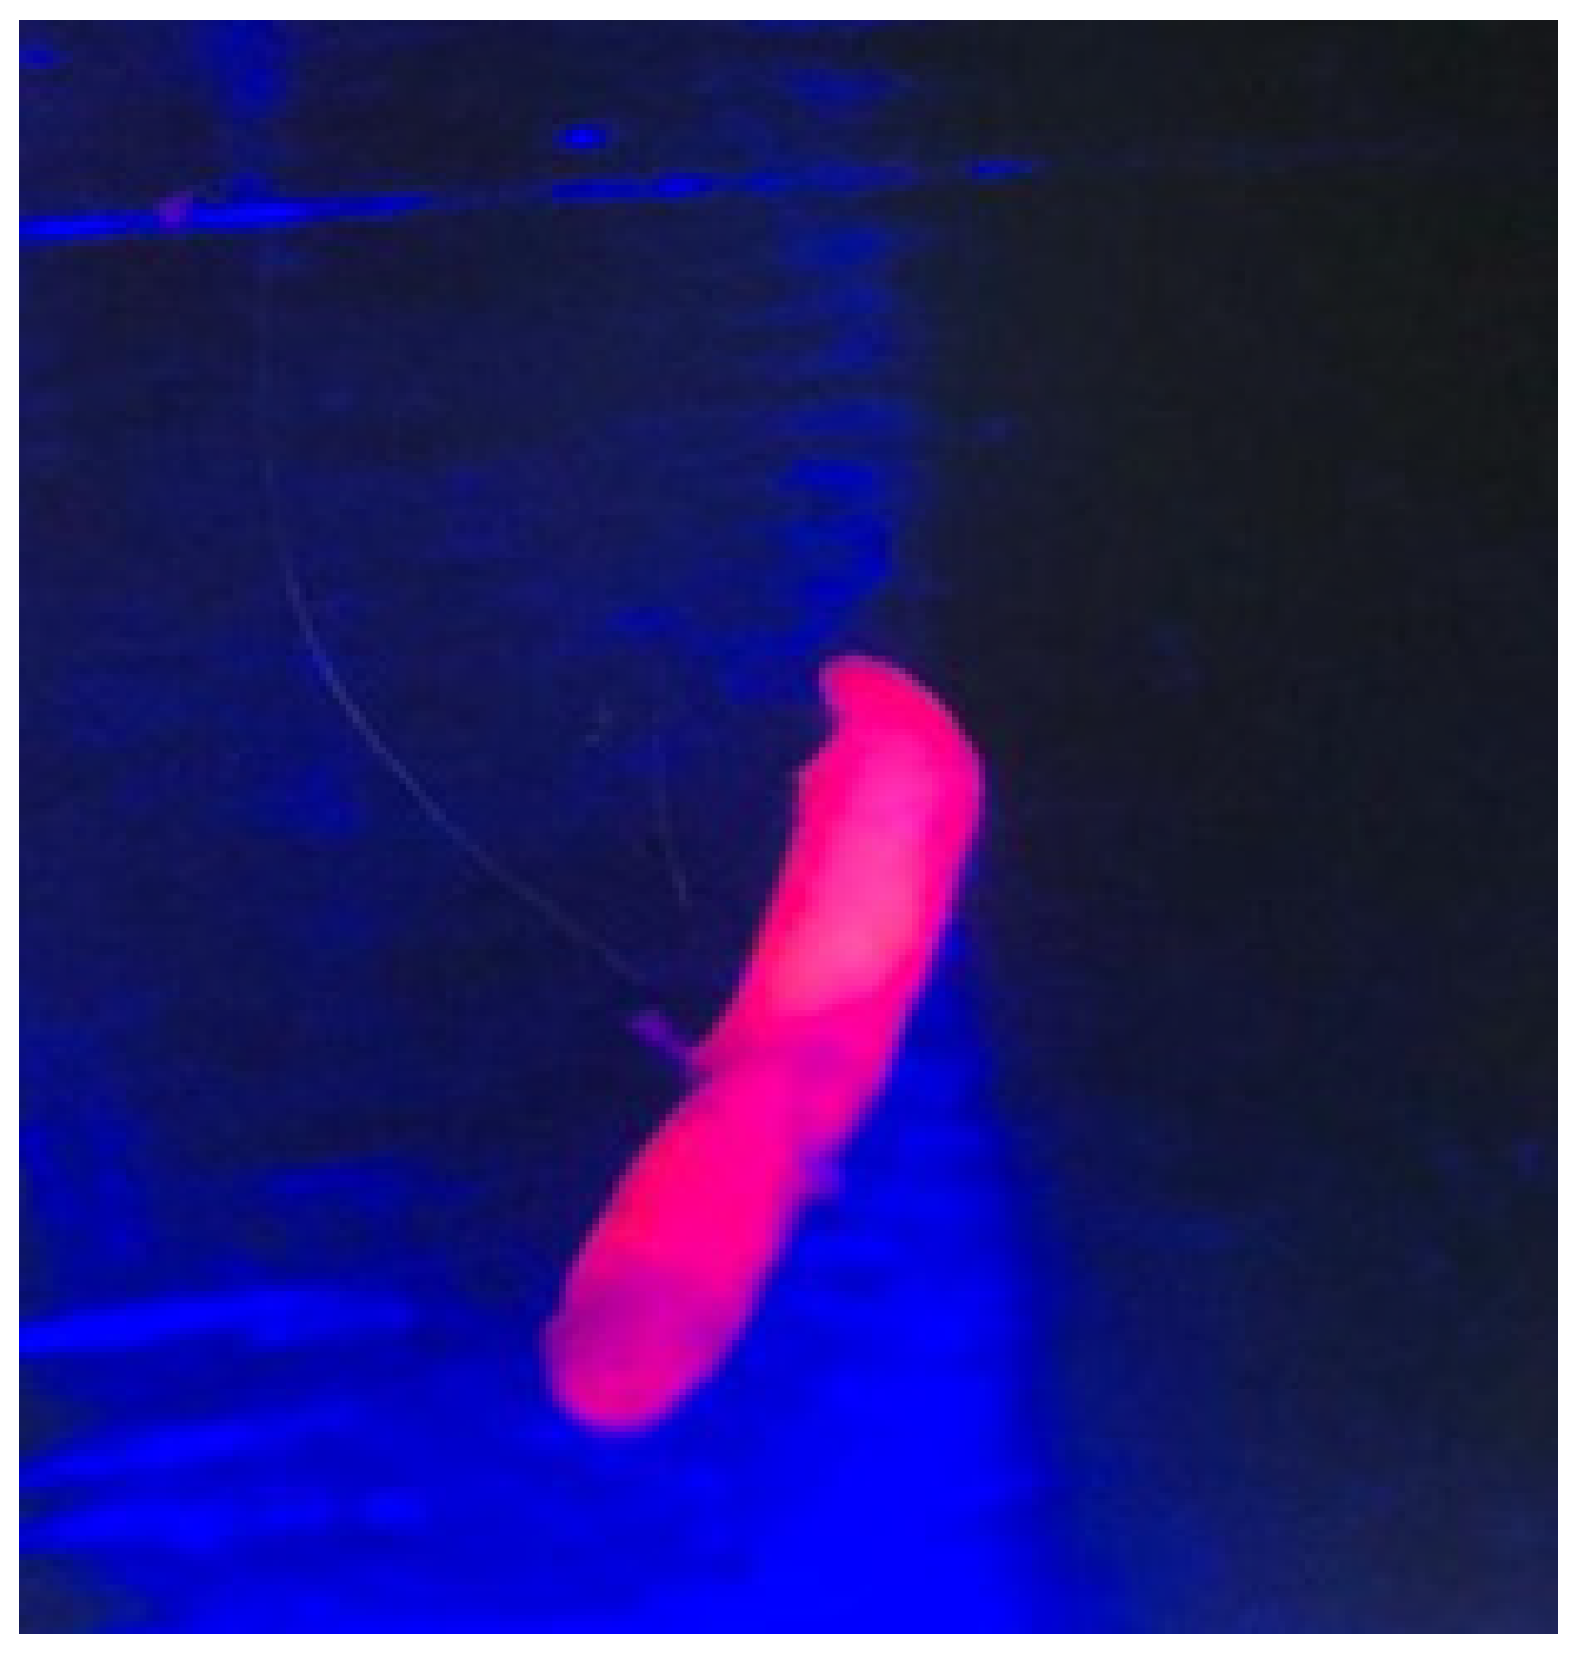

- Walter, S.; Susanne, S.; Simon, W.; Herbert, S.; Clemens, F.; Claudia, G.; Alwin, E.G.; Rainer, K.; Hans, J.R. Intraoperative Detection of Malignant Gliomas by 5-Aminolevulinic Acid-Induced Porphyrin Fluorescence. Neurosurgery 1998, 42, 518–526. [Google Scholar] [CrossRef] [PubMed]

- Yamaguchi, F.; Takahashi, H.; Teramoto, A. Photodiagnosis for Frameless Stereotactic Biopsy of Brain Tumor. Photodiagnosis Photodyn. Ther. 2007, 4, 71–75. [Google Scholar] [CrossRef] [PubMed]

- Malinova, V.; von Eckardstein, K.; Mielke, D.; Rohde, V. Diagnostic Yield of Fluorescence-Assisted Frame-Based Stereotactic Biopsies of Intracerebral Lesions in Comparison with Frozen-Section Analysis. J. Neurooncol. 2020, 149, 315–323. [Google Scholar] [CrossRef]

- Shofty, B.; Richetta, C.; Haim, O.; Kashanian, A.; Gurevich, A.; Grossman, R. 5-ALA-Assisted Stereotactic Brain Tumor Biopsy Improve Diagnostic Yield. Eur. J. Surg. Oncol. 2019, 45, 2375–2378. [Google Scholar] [CrossRef] [PubMed]

- von Campe, G.; Moschopulos, M.; Hefti, M. 5-Aminolevulinic Acid-Induced Protoporphyrin IX Fluorescence as Immediate Intraoperative Indicator to Improve the Safety of Malignant or High-Grade Brain Tumor Diagnosis in Frameless Stereotactic Biopsies. Acta Neurochir. 2012, 154, 585–588. [Google Scholar] [CrossRef] [PubMed]

- Widhalm, G.; Minchev, G.; Woehrer, A.; Preusser, M.; Kiesel, B.; Furtner, J.; Mert, A.; Di Ieva, A.; Tomanek, B.; Prayer, D.; et al. Strong 5-Aminolevulinic Acid-Induced Fluorescence Is a Novel Intraoperative Marker for Representative Tissue Samples in Stereotactic Brain Tumor Biopsies. Neurosurg. Rev. 2012, 35, 381–391. [Google Scholar] [CrossRef] [PubMed]